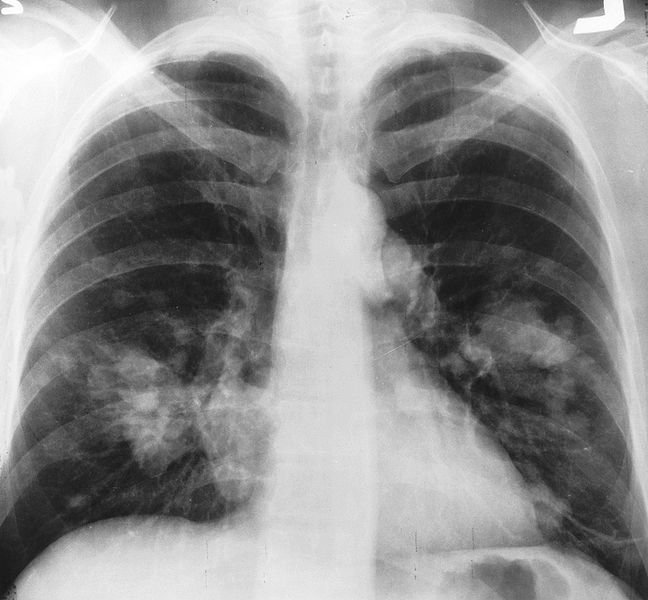

X-Ray

Lungs cancer